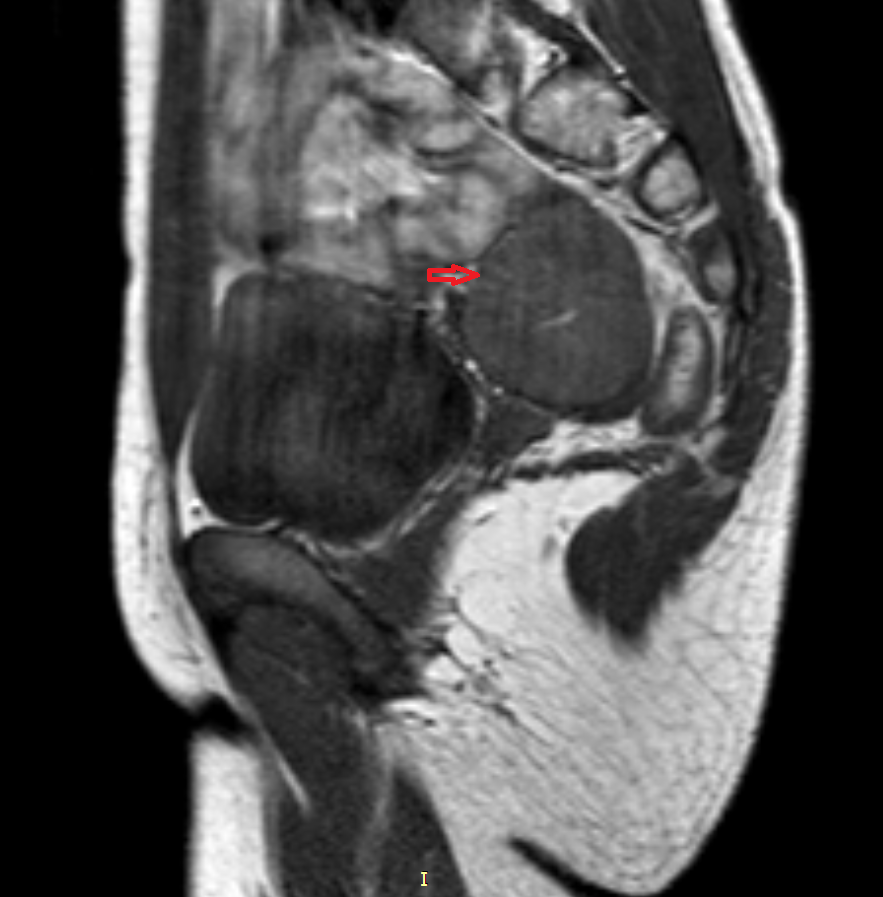

а)

Risunok3a.png

б)

Risunok3b.pngРисунок 3. – тератома яичника а –УЗИ, б - МРТ.